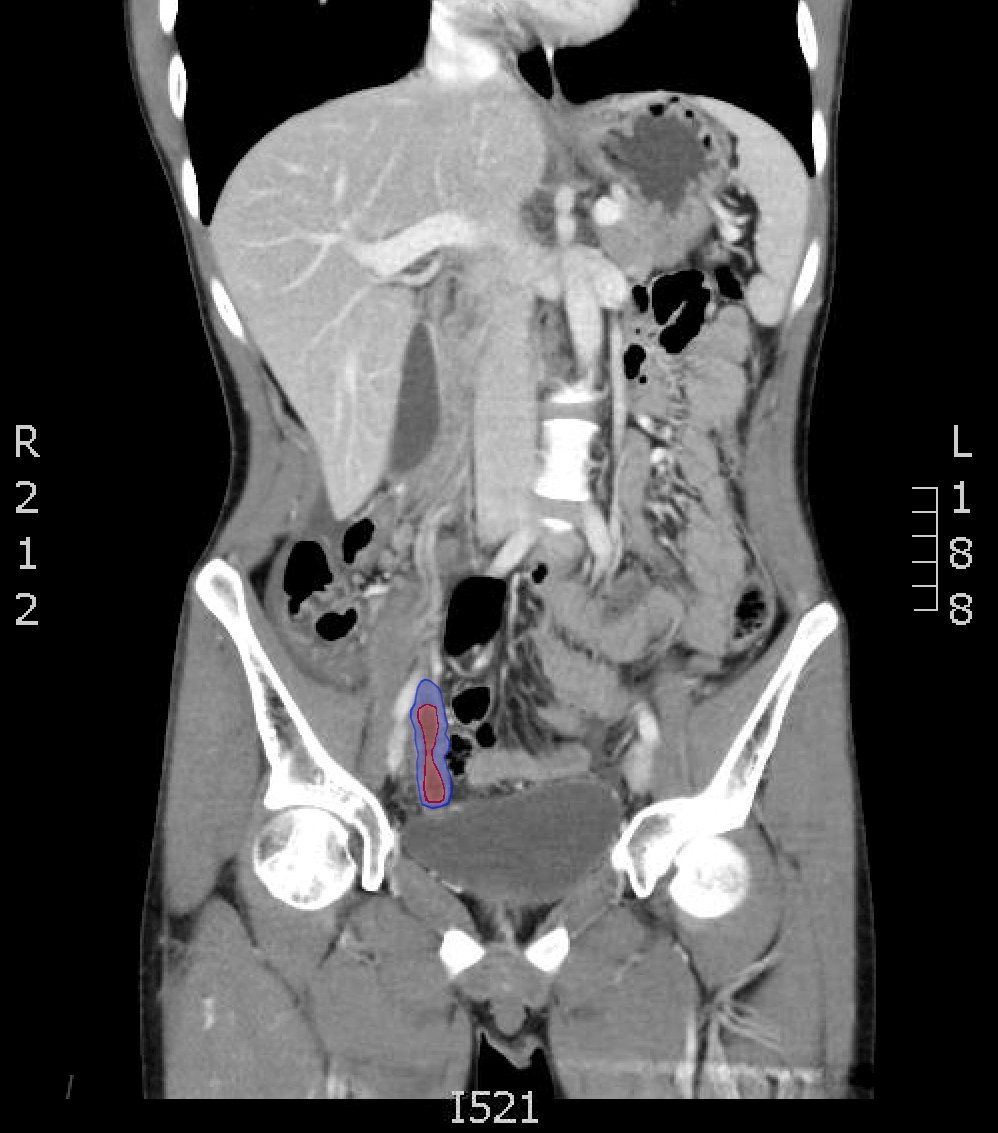

The CT abdomen/pelvis with intravenous contrast shows a dilated appendix (see red outline) with thickened, hyperenhancing wall (see blue outline) best visualized in the axial and coronal planes.